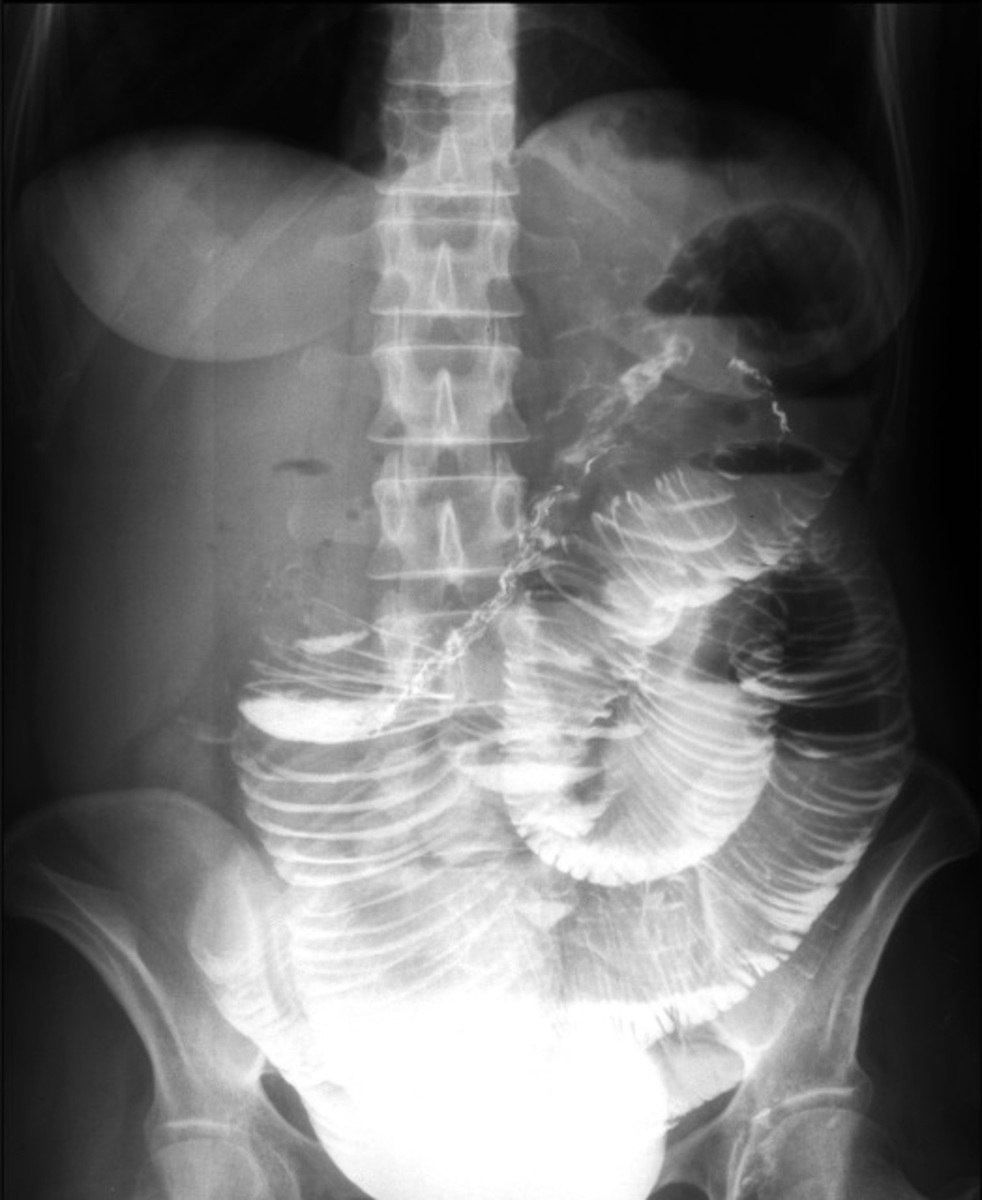

Фото пресс-службы ОДКБ города Владимира

В ходе срочной операции врачи хирургического отделения ОДКБ выявили два многоцилиндровых инвагината. Врачам удалось провести расправление обоих инвагинатов. В составе одного из них была обнаружена опухоль размерами 5*5*5 см, которая была удалена во время операции.В ОДКБ уточняют, что девочка уже выписана домой и чувствует себя хорошо.

Инвагинация кишечника — это внедрение одной части кишки в другую, в результате которого развивается кишечная непроходимость. Чаще инвагинация кишечника встречается у детей в возрасте от 4 до 9 месяцев (85 – 90% случаев). Мальчики страдают в два раза чаще девочек.